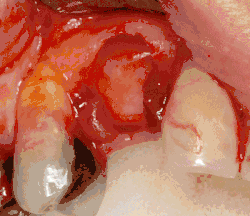

Soft tissue (gingiva) reconstruction

The gingiva surrounding a tooth has a 2–3 mm band of bright pink, very strong attached mucosa, then a darker, larger area of unattached mucosa that folds into the cheeks. When replacing a tooth with an implant, a band of strong, attached gingiva is needed to keep the implant healthy in the long-term. This is especially important with implants because the blood supply is more precarious in the gingiva surrounding an implant, and is theoretically more susceptible to injury because of a longer attachment to the implant than on a tooth (a longer biologic width).[64]: 629–633

When an adequate band of attached tissue is absent, it can be recreated with a soft tissue graft. There are four methods that can be used to transplant soft tissue. A roll of tissue adjacent to an implant (referred to as a palatal roll) can be moved towards the lip (buccal), gingiva from the palate can be transplanted, deeper connective tissue from the palate can be transplanted or, when a larger piece of tissue is needed, a finger of tissue based on a blood vessel in the palate (called a vascularized interpositional periosteal-connective tissue (VIP-CT) flap) can be repositioned to the area.[58]: 113–188 Xenogeneic collagen matrices are used for gingival augmentation after dental implantation.[65][66]

Additionally, for an implant to look esthetic, a band of full, plump gingiva is needed to fill in the space on either side of implant. The most common soft tissue complication is called a black triangle, where the papilla (the small triangular piece of tissue between two teeth) shrinks back and leaves a triangular void between the implant and the adjacent teeth. Dentists can only expect 2–4 mm of papilla height over the underlying bone. A black triangle can be expected if the distance between where the teeth touch and bone is any greater.[50]: 81–84